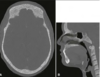

What is this radiographical finding?

Metastatic Carcinoma to Jaw Bones

C. Periapical image of a metastatic lesion of breast carcinoma; note the irregular widening of the periodontal membrane spaces and patchy sclerotic bone reaction, especially around the roots of the molars